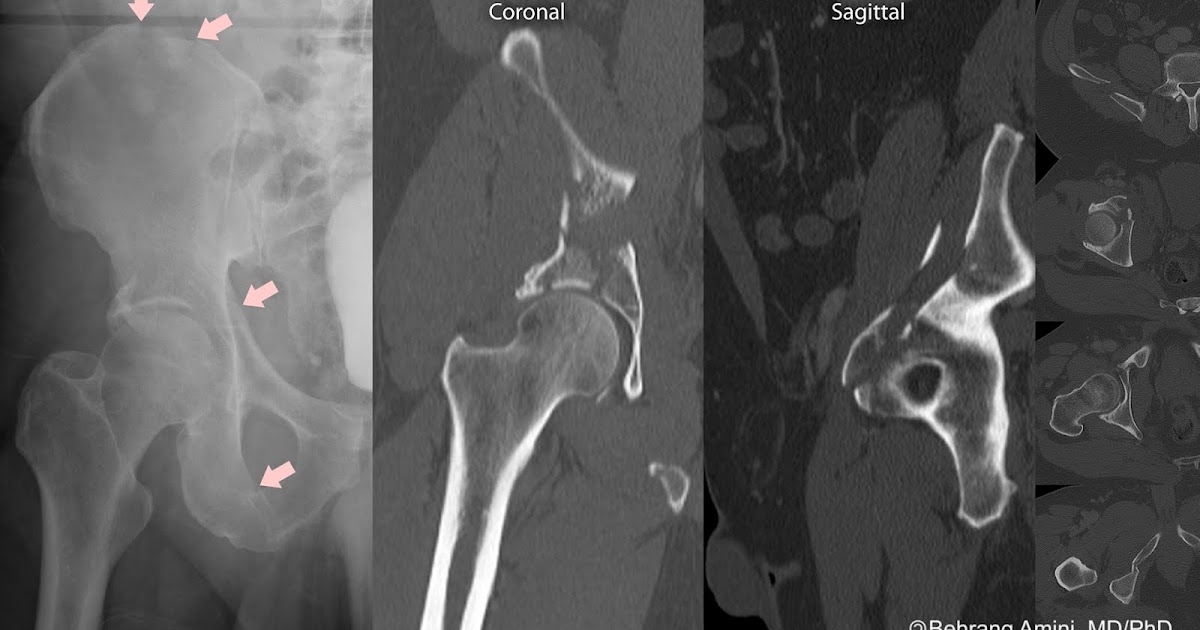

posterior acetabular fracture Radiology imaging, Medical studies Acetabular Fracture X Ray In this article, the five most common acetabular fractures are reviewed: In this article, the five most common acetabular fractures are reviewed: The elementary (or elemental) patterns fracture the innominate bone through the acetabulum into two major fragments. Standard radiographic evaluation • obtaining and understanding standard views • identifying and understanding. Acetabulum fractures are pelvis fractures that involve the articular. Acetabular Fracture X Ray.